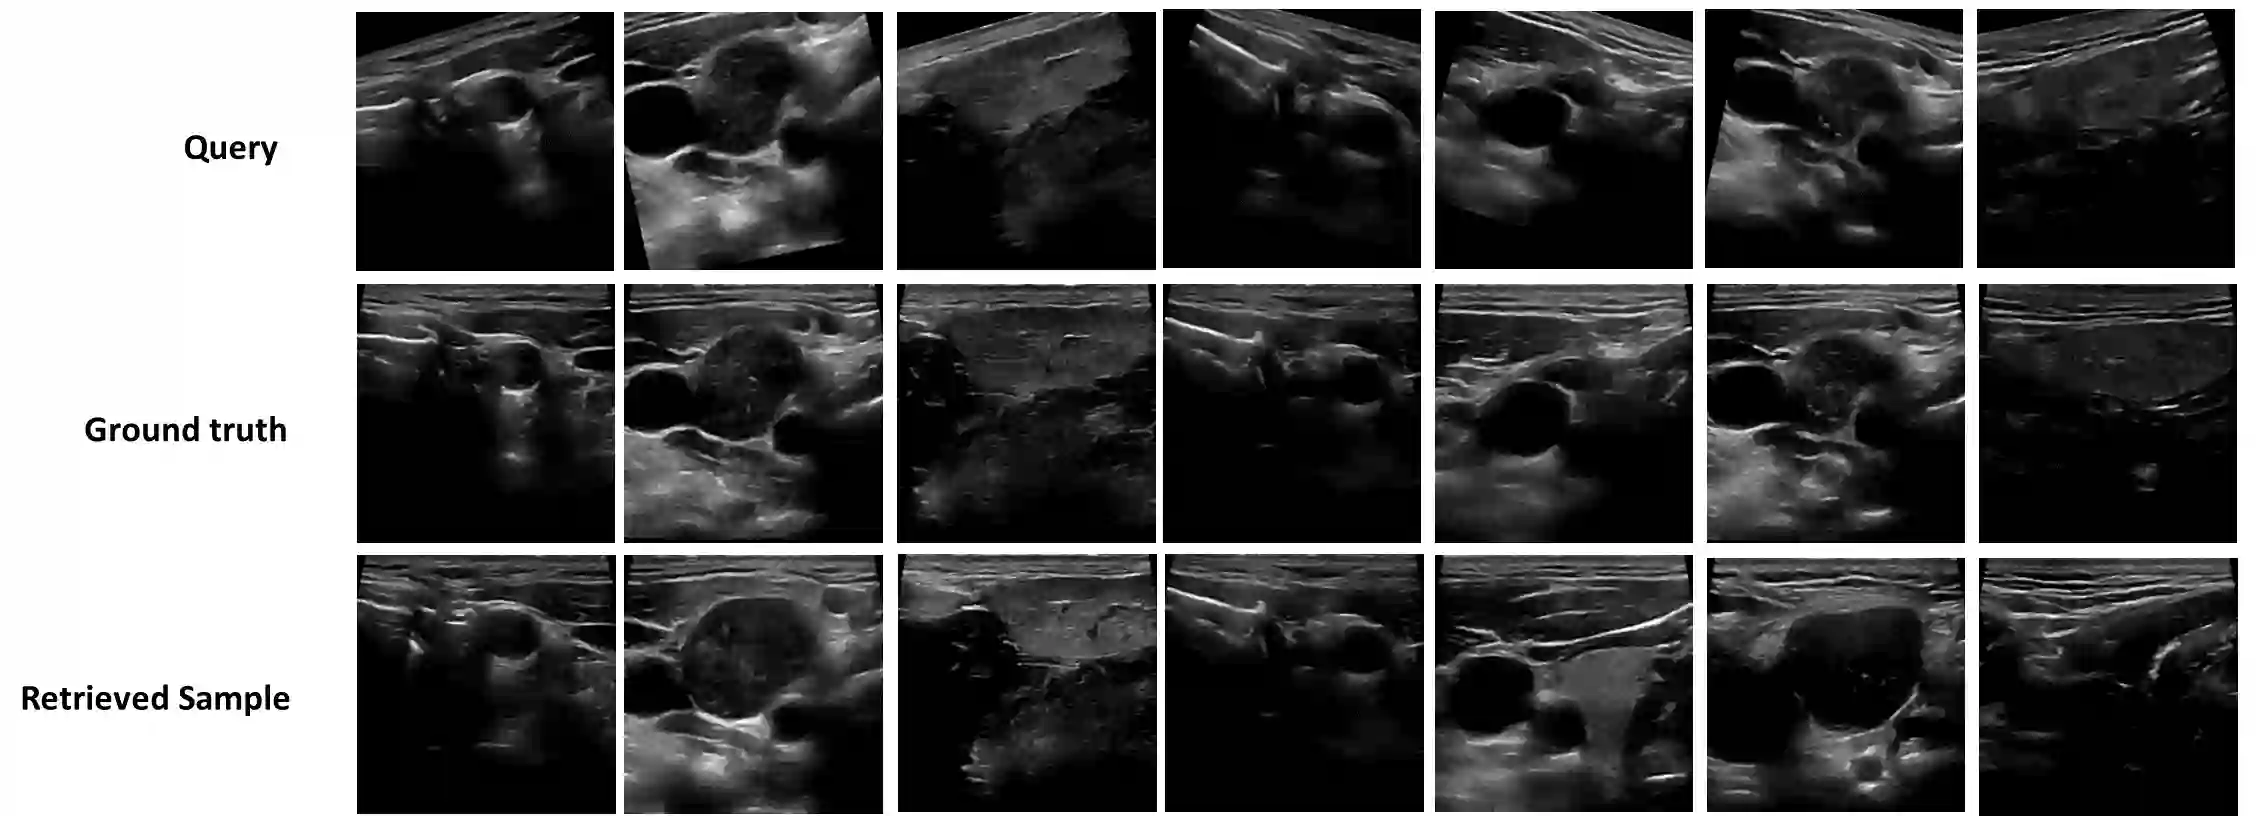

Purpose: Intraoperative ultrasound (US) can enhance real-time visualization in transoral robotic surgery. The surgeon creates a mental map with a pre-operative scan. Then, a surgical assistant performs freehand US scanning during the surgery while the surgeon operates at the remote surgical console. Communicating the target scanning plane in the surgeon's mental map is difficult. Automatic image retrieval can help match intraoperative images to preoperative scans, guiding the assistant to adjust the US probe toward the target plane. Methods: We propose a self-supervised contrastive learning approach to match intraoperative US views to a preoperative image database. We introduce a novel contrastive learning strategy that leverages intra-sweep similarity and US probe location to improve feature encoding. Additionally, our model incorporates a flexible threshold to reject unsatisfactory matches. Results: Our method achieves 92.30% retrieval accuracy on simulated data and outperforms state-of-the-art temporal-based contrastive learning approaches. Our ablation study demonstrates that using probe location in the optimization goal improves image representation, suggesting that semantic information can be extracted from probe location. We also present our approach on real patient data to show the feasibility of the proposed US probe localization system despite tissue deformation from tongue retraction. Conclusion: Our contrastive learning method, which utilizes intra-sweep similarity and US probe location, enhances US image representation learning. We also demonstrate the feasibility of using our image retrieval method to provide neck US localization on real patient US after tongue retraction.